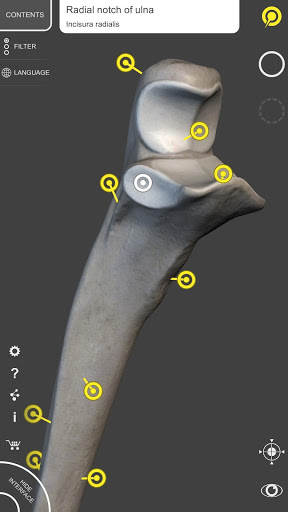

Mỗi xương của bộ xương người đã được tái tạo ở dạng 3D, bạn có thể xoay và phóng to từng mô hình và quan sát chi tiết từ mọi góc độ.

Bằng cách chọn mô hình hoặc ghim, bạn sẽ được hiển thị các thuật ngữ liên quan đến bất kỳ bộ phận giải phẫu cụ thể nào, bạn có thể chọn từ 12 ngôn ngữ và hiển thị các thuật ngữ bằng hai ngôn ngữ cùng lúc.

• Xoay và Phóng to mọi mô hình trong không gian 3D

• Ghim tương tác cho phép trực quan hóa thuật ngữ liên quan đến mọi chi tiết giải phẫu